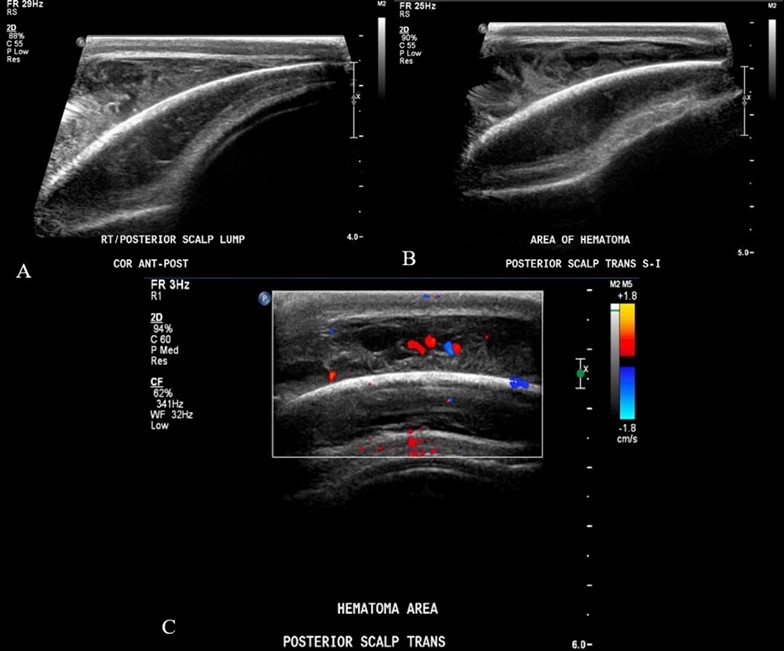

From a musculoskeletal standpoint, MRIs of the cervical, thoracic, and lumbar spine were within normal limits. The patient was started on scheduled acetaminophen for pain management. A CT of the head without contrast showed right high convexity scalp soft tissue swelling without acute intracranial abnormality (Figure 1A – 1F). A complete bone survey was negative for sources of trauma (Figure 2B – 2I) but did note calvarial soft tissue edema (Figure 2A). A head ultrasound confirmed the fluctuance on the patient’s skull to be a subgaleal hemorrhage (Figure 3A – 3C) of 9 mm thickness at its greatest.

Figure 3A – 3C.Ultrasound soft tissue head using multiplanar gray scale and color Doppler images. The superficial subcutaneous soft tissue appears homogeneous and uniform thickness. There is a layer of heterogeneous echogenicity deep to the subcutaneous layer, on the surface of the bone which appears retained by an echogenic capsule or membrane. This measures up to 9 mm greatest thickness. The size of the collection is greater than the transducer can measure. Additional images performed to include the edges of the hemorrhage show uplifting of the galea consistent with subgaleal location. The cranial sutures are not adequately included.

Ultrasound soft tissue head using multiplanar gray scale and color Doppler images. The superficial subcutaneous soft tissue appears homogeneous and uniform thickness. There is a layer of heterogeneous               echogenicity deep to the subcutaneous layer, on the surface of the bone which appears retained by an echogenic capsule or membrane. This measures up to 9 mm greatest thickness. The size of the collection is greater than the transducer can measure. Additional images performed to include the edges of the hemorrhage show uplifting of the galea consistent with subgaleal location. The cranial sutures are not adequately included.